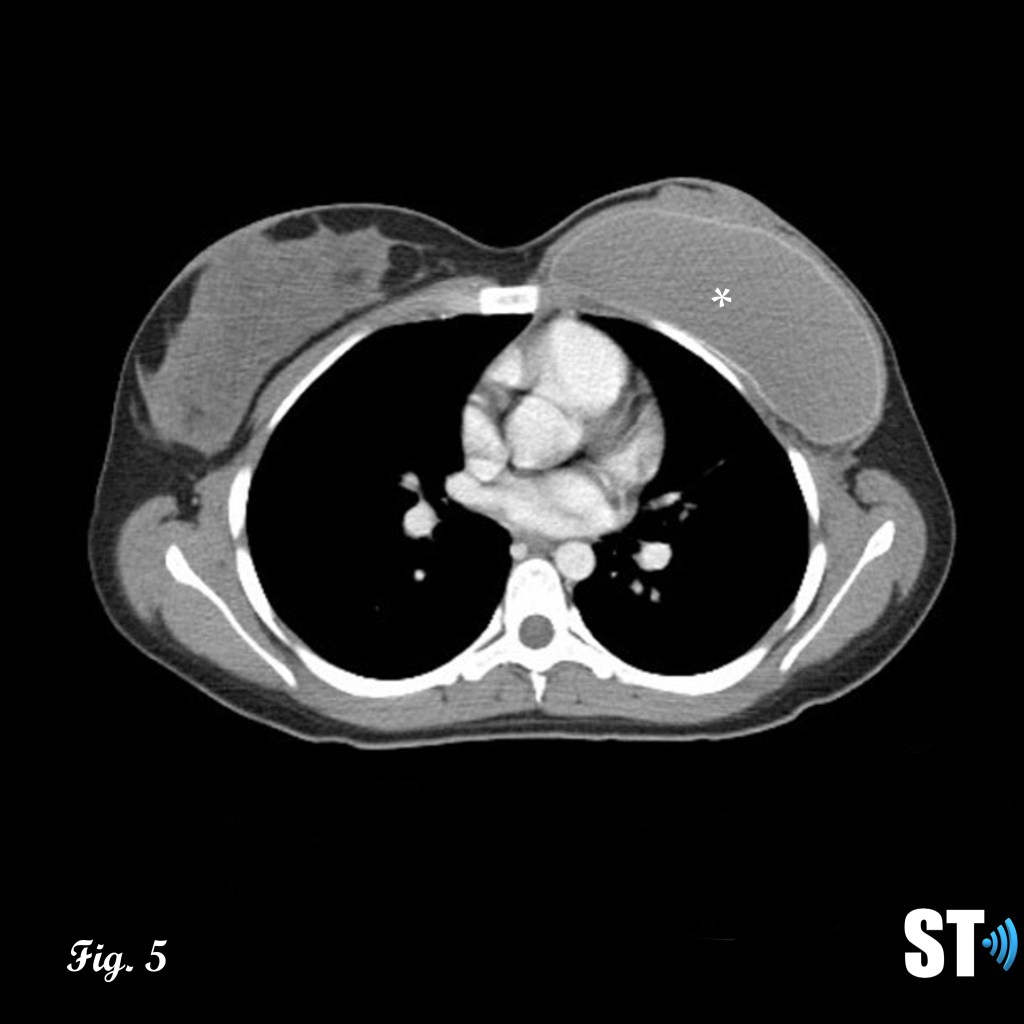

Figure 4-5 follow up post lumpectomy with post-surgical changes (air, red arrow) lesion was found to be malignant phyllodes resulting in mastectomy Fig.5 with breast implant in place (white asterisk).